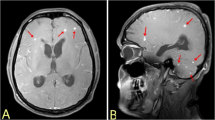

We analyzed 34 reports describing 39 individuals. The majority (85%) had a duration of illness of one month or less. Upper motor neuron paraparesis was the most common neurological manifestation (69.2%), followed by areflexic paraparesis (15.3%). Paradoxical reactions occurred in 20.5% of cases. Microbiological confirmation was achievable in approximately 77% of cases. Neuroimaging abnormalities were present in 41% of cases, and chest imaging abnormalities in 53.9%. Longitudinally-extensive hyperintensities in cervical and thoracic regions were common spinal imaging abnormalities. Central nervous system tuberculosis was confirmed in 47.7% of cases, while pulmonary and disseminated tuberculosis were each found in 25.6%. Improvement was noted in 87.2% of cases, while 10.3% did not improve or died.